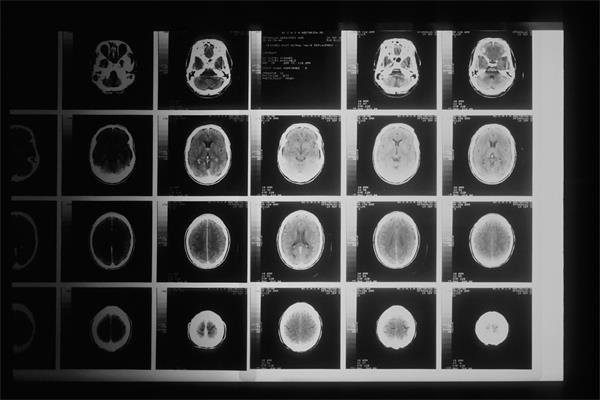

Yapay Zeka Kadın ve Erkek Beyinlerini %90’ı Aşan İsabetle Tanımlayabiliyor Stanford Üniversitesi Tıp Fakültesi'nde çalışan araştırmacıların yaptığı yeni bir çalışma, beyin taramalarıyla bir kişinin kadın mı yoksa erkek mi olduğunu %90'dan fazla doğrulukla tespit edebilen yapay zeka modelini ortaya koyuyor. Bu bulgular, uzun süredir süregelen insan beyninde cinsiyet farklılıklarının varlığına dair tartışmalara ışık tutuyor. Stanford Bilişsel Sinirbilim ve Sistemler Sinirbilimi Laboratuvarı müdürü ve psikiyatri profesörü Vinod Menon, “Bu çalışmanın temel motivasyonlarından biri, cinsiyetin insan beyninin gelişiminde, yaşlanmasında ve nöropsikiyatrik rahatsızlıkların ortaya çıkmasında önemli bir rol oynamasıdır,” diyor. Araştırmacılar, yeni modelin kadın ve erkek beyinlerini ayırt etmede özellikle striyatum ve limbik ağ gibi beyin bölgelerine odaklandığını belirtiyor. Araştırmacılar, modelin beyin taramalarının kadına mı yoksa erkeğe mi ait olduğunu neredeyse her zaman doğru bir şekilde belirleyebildiğini gözlemledi. Bu model, beynin içerisindeki cinsiyetle ilişkilendirilebilecek belirli örüntüleri tanımlama konusunda diğer modellere göre üstün bir performans gösterdi. Menon ve ekibi, bu yapılan çalışmanın, beyindeki cinsiyetle ilişkilendirilebilecek farklılıkların anlaşılmasında önemli bir adım olduğunu ve modelin gelecekte nöropsikiyatrik hastalıkların ve bilişsel yeteneklerin incelenmesinde kullanılabileceğini vurguluyor. Modelin açıklanabilir yapay zeka aracılığıyla nasıl çalıştığının detayları da gelecek araştırmalar için önemli bir kapı açıyor. #YapayZeka #Beyin #Cinsiyet #Nöropsikiyatri #StanfordÜniversitesiİnternet Hız Testi